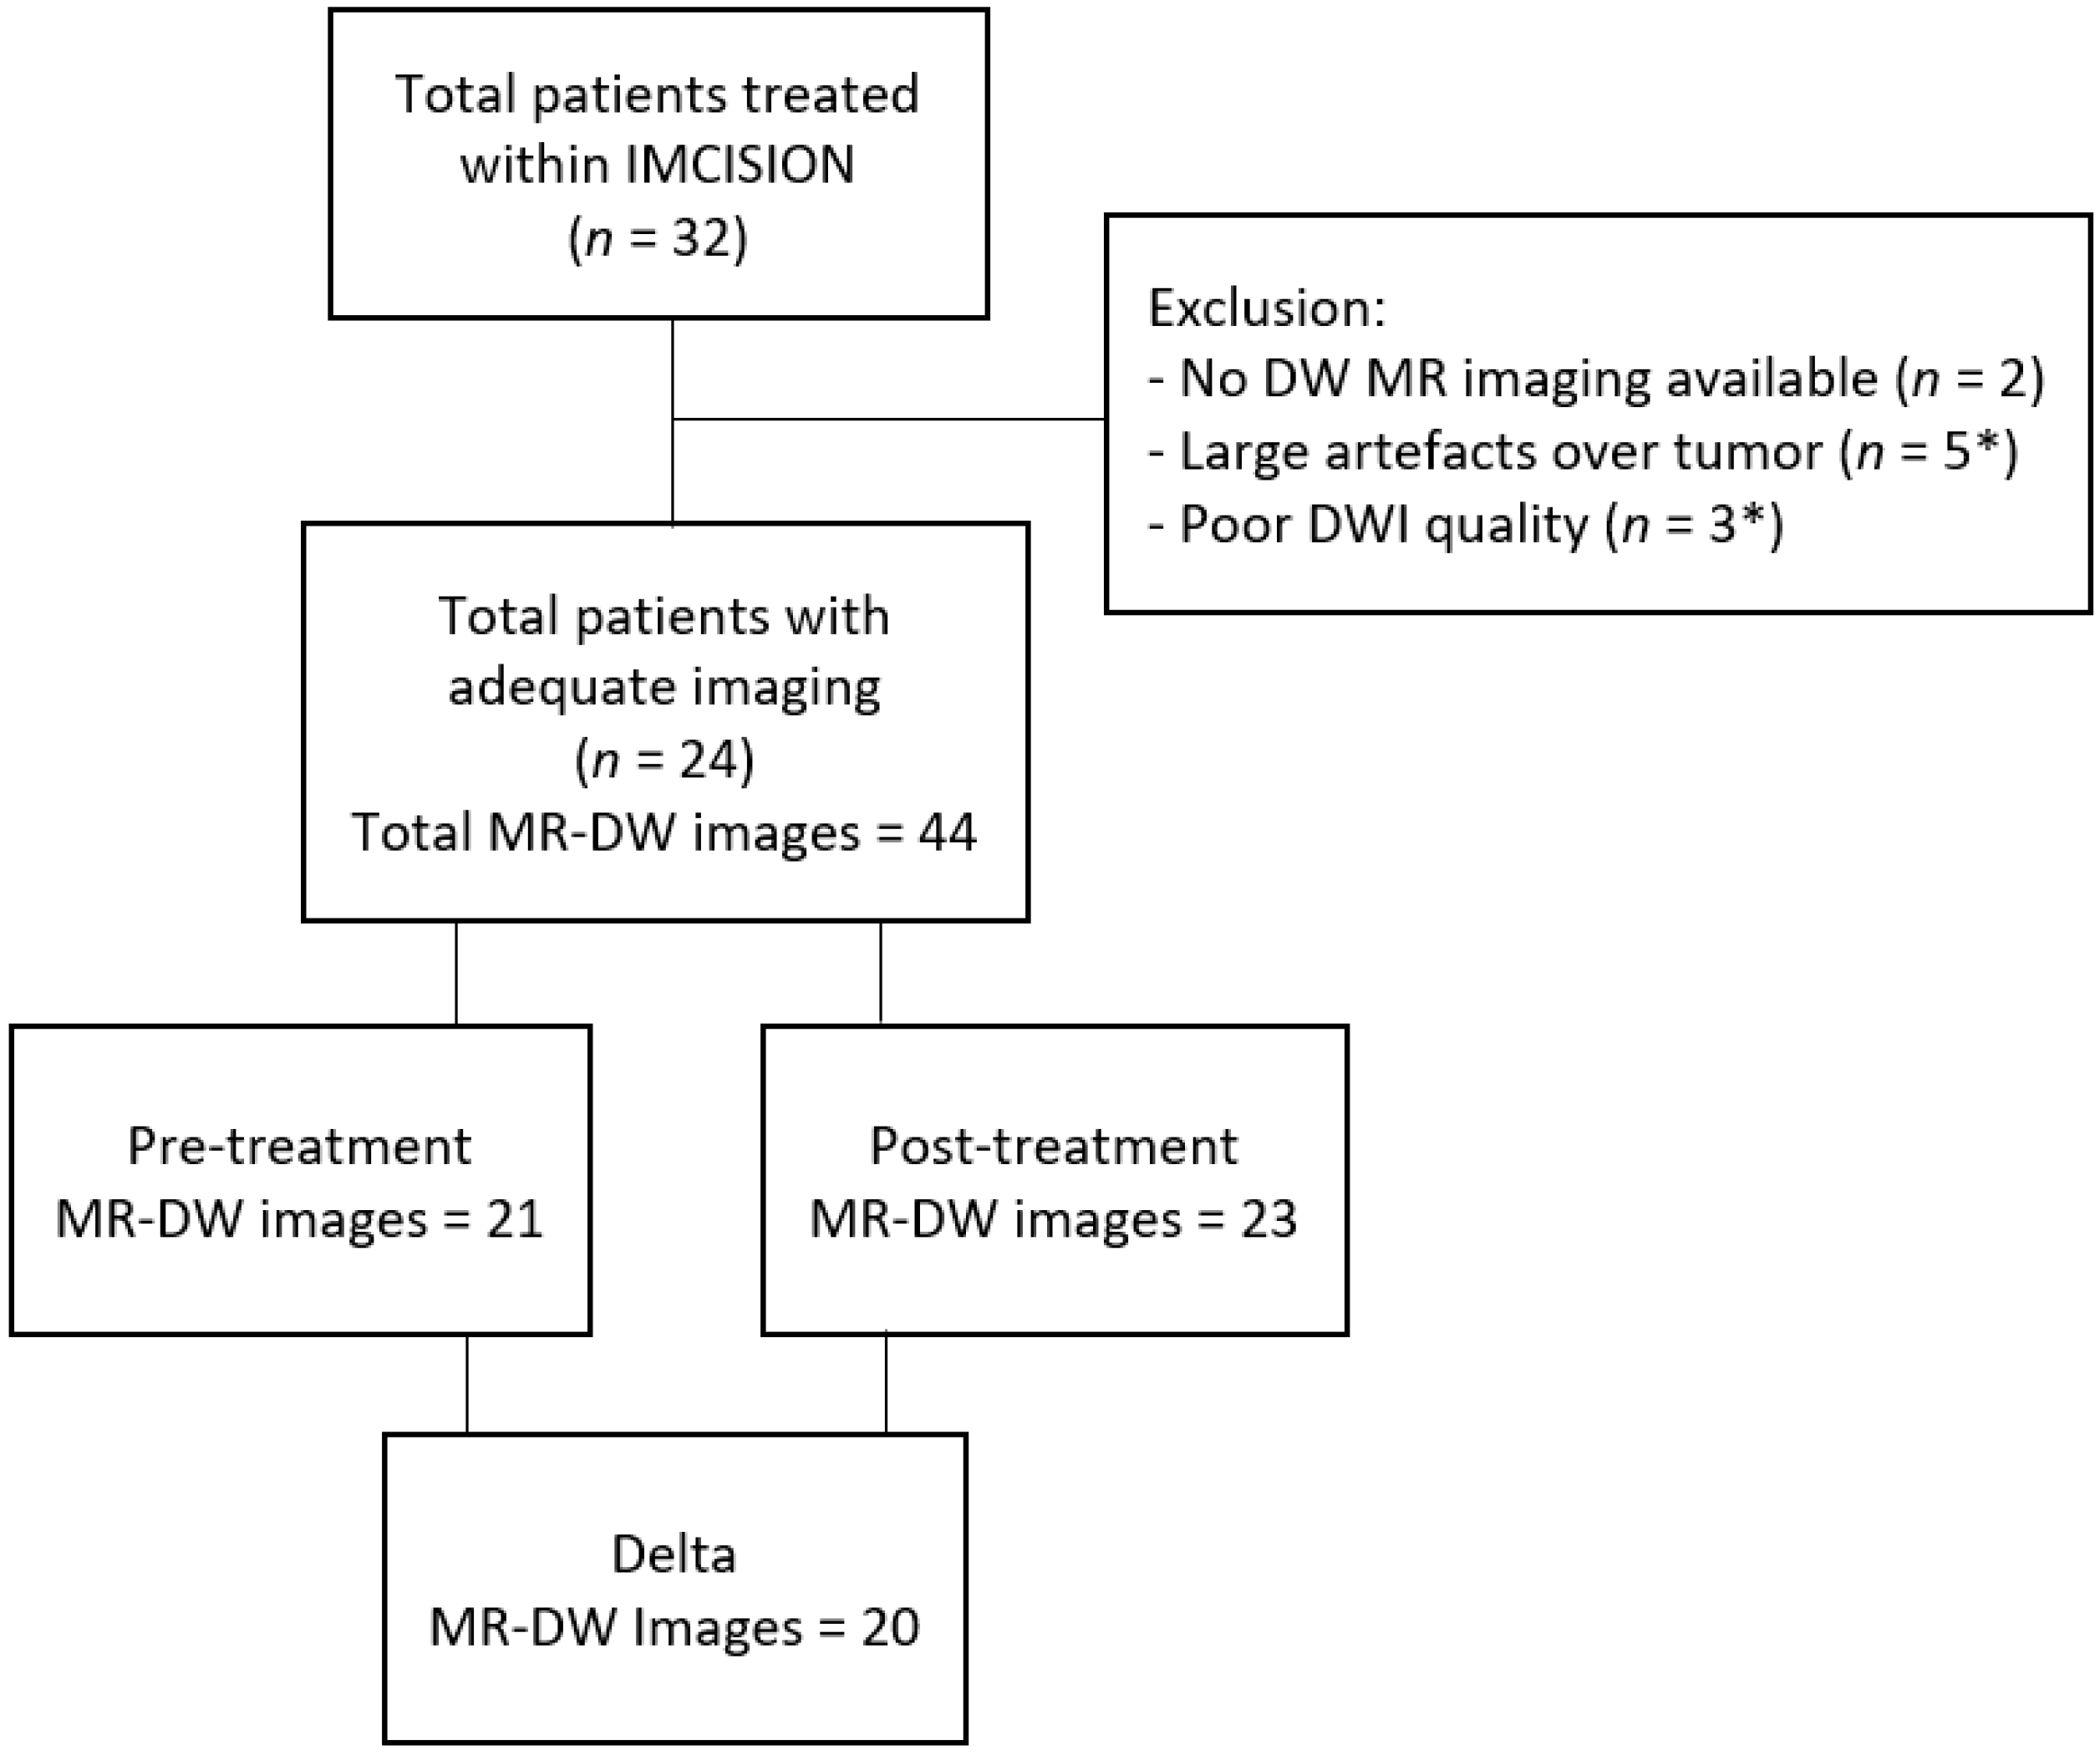

2.1. Patient Population and Trail Treatment Details